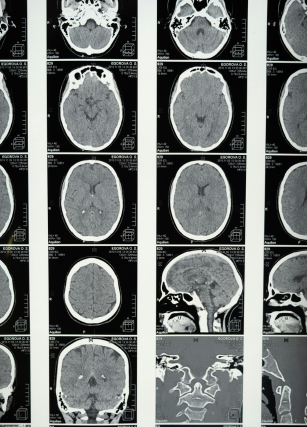

Como primer punto a destacar, la negligencia espacial unilateral constituye una afección neurológica que surge comúnmente después de una lesión en el hemisferio derecho del cerebro, usualmente, un accidente cerebrovascular (ACV), afectando hasta el 50% de los sobrevivientes. Los personas afectadas por este cuadro ignoran o tienen dificultades para percibir estímulos en su lado izquierdo, lo que afecta actividades como caminar, vestirse, o reconocer objetos en ese lado.

Aunque generalmente se asocia con daño en el hemisferio derecho, también puede ocurrir tras lesiones en el hemisferio izquierdo. Entonces, podemos afirmar que esta patología no se debe a déficits sensoriales, sino a una falla en la atención y la percepción espacial, lo que lo convierte en un problema complejo que requiere intervenciones específicas.